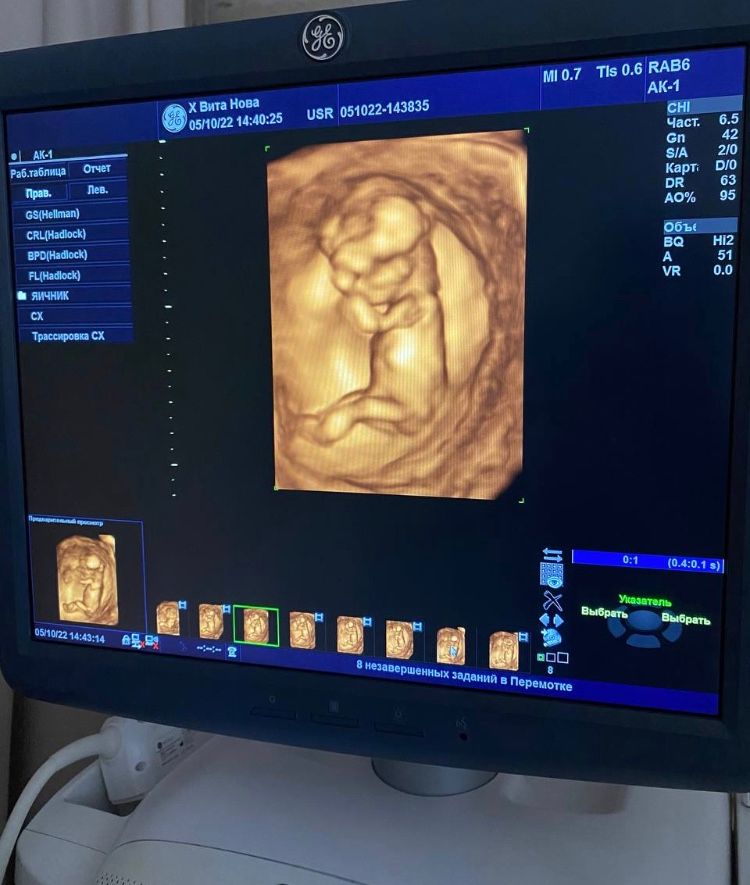

Анастасия Попова, Изображение 4д делала,но пол не увидели(

07.10.2022